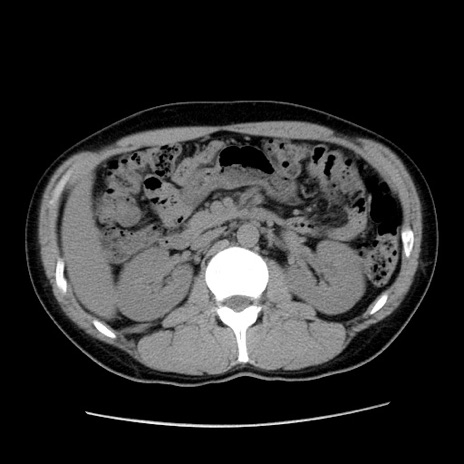

症例36(横断像)

【症例】20歳代 男性

【主訴】心窩部痛

【現病歴】今朝より上腹部痛あり。一旦軽快していたが再度出現したため救急要請。昨日夕に白身の魚を含む刺身を食べた。

【身体所見】BP 136/89mmHg、HR 74/min、BT 37.0℃、腹部:膨満、軟、心窩部に圧痛あり。反跳痛なし、筋性防御なし、腸雑音やや亢進あり。

【データ】WBC 17700、CRP 0.48